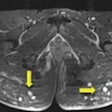

When buttock fillers and injections go wrong